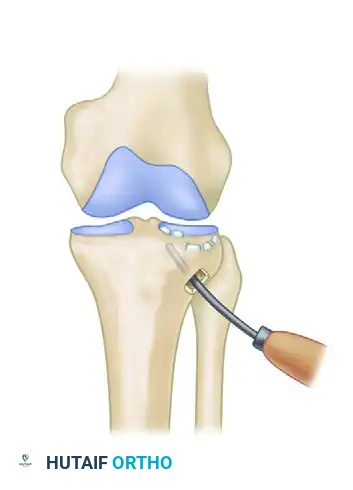

- Elevate the depressed fragments through a percutaneous metaphyseal window using a cannulated impactor guided by an ACL tibial drill guide.